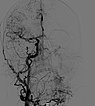

In der Spätphase der DSA (laterale Ansicht) über die linke A. carotis interna. Nach erfolgreicher mehrfacher Embolisation ist auch die Versorgung des Nidus der AVM über diese kritischen Äste verschlossen und die A. ophtalmica erhalten.